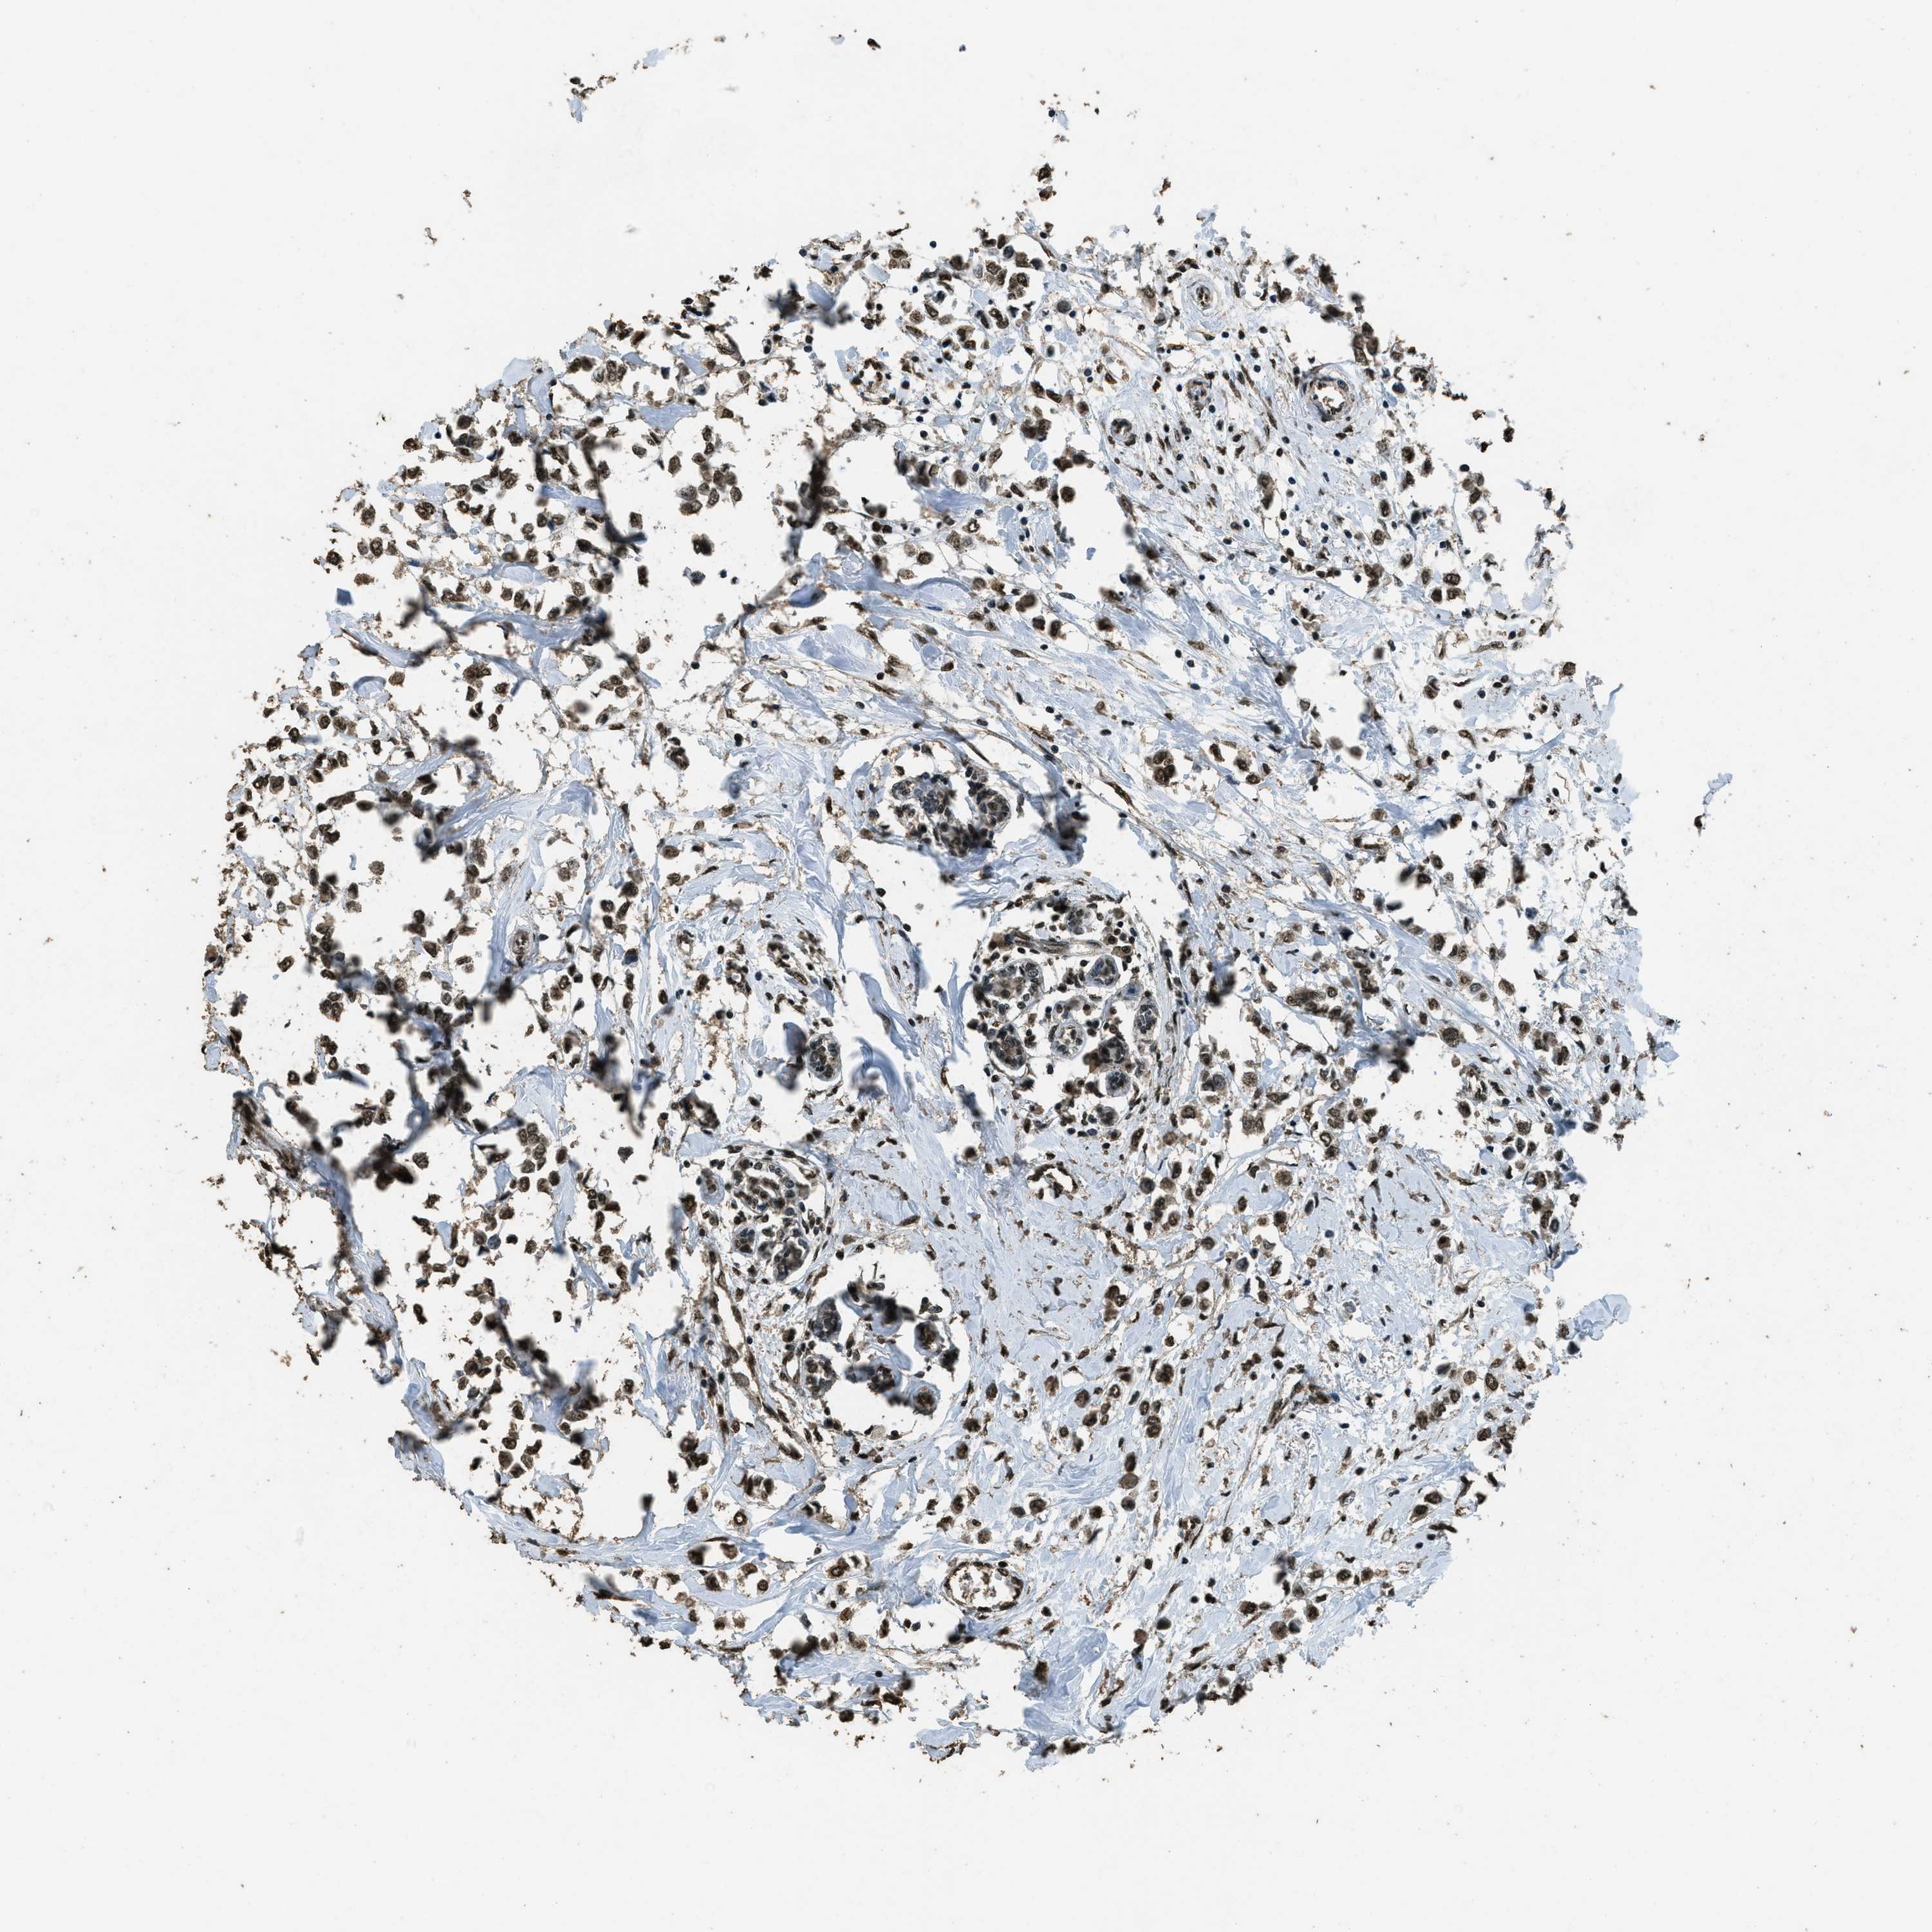

BRCA TCGA BRCA VALIDATION PROTEIN EXPRESSION

ANTIBODIES

AND

VALIDATION